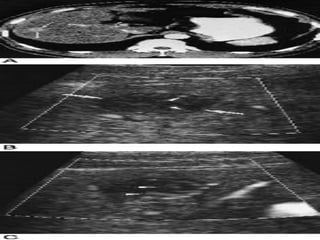

■Siªu ©m bông:

+Khèi u: ↓ ©m, ↑ ©m, hçn hîp ©m, quÇng halo

+X©m lÊn TM cöa, TM trªn gan

+D·n ®êng mËt trong gan ë phÝa trªn khèi u

■CT bông cã tiªm c¶n quang

+Tríc khi tiªm c¶n quang: khèi u ↓tû träng, canxi

ho¸ t¹i khèi u, x©m lÊn h¹ch, mµng bông

+Sau tiªm c¶n quang: khèi u ↑tû träng (t¨ng m¹ch

m¸u), x©m lÊn TM cöa vµ TM trªn gan

■MRI: khèi u tÝn hiÖu ë T1 vµ tÝn hiÖu ë T2

■M« bÖnh häc: Chäc hót TB hay ST gan díi sù híng dÉn cña

siªu ©m hay CT